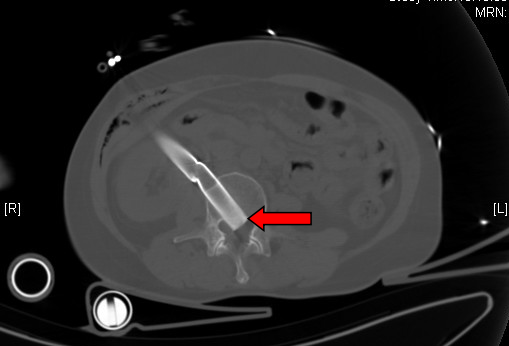

CT重建显示钢管(箭头处)刺入脊柱

“患者是腹部穿透伤,加多发骨折,脊髓损伤不除外。”张鹏初步判断患者病情后陪同患者前往进行全身CT检查。检查结果显示,患者右侧肋骨骨折合并气胸、右侧股骨干骨折、左侧髌骨骨折、左侧胫腓骨骨折、左侧跖骨骨折,腹部的钢管经过肝肾之间插入腰椎,影像上能看到已直达椎间孔。幸运的是腹腔内未见明显积液及游离气体,“这意味着患者胃肠道及重要的实质脏器未受到重大损伤,应该暂时没有生命危险。”张鹏说。

CT显示钢管刺入脊柱(箭头处)